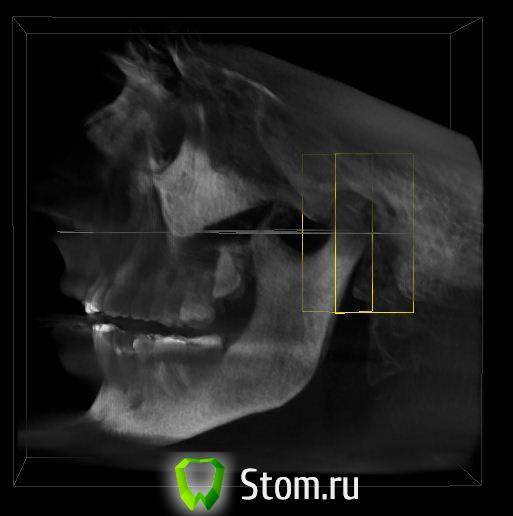

Oleg-Gru Опубликовано 22 ноября, 2011 Автор Поделиться Опубликовано 22 ноября, 2011 Да уж... Почему-то вспомнилась поговорка о благих намерениях устилающих дорогу в ад. На самом деле есть более чем один повод разобраться с ВНЧС. Несколько лет страдаю от ушного шума. Говорят, что это тоже может быть связано с суставом. К сожалению боковой телерентгенограммы пока нет. Есть только КТ. Можно что-то сказать по этим снимкам? Если нет, то сделаю рентген и повешу тут через пару дней. Ссылка на комментарий

Снежана Опубликовано 22 ноября, 2011 Поделиться Опубликовано 22 ноября, 2011 Да уж... Почему-то вспомнилась поговорка о благих намерениях устилающих дорогу в ад. На самом деле есть более чем один повод разобраться с ВНЧС. Несколько лет страдаю от ушного шума. Говорят, что это тоже может быть связано с суставом. К сожалению боковой телерентгенограммы пока нет. Есть только КТ. Можно что-то сказать по этим снимкам? Если нет, то сделаю рентген и повешу тут через пару дней. здесь вам никто анализ делать и считать ничего не будет по интернету. возможно и достаточно КТ, смотря какое оно у вас, это будет решать лечащий врач. Ссылка на комментарий